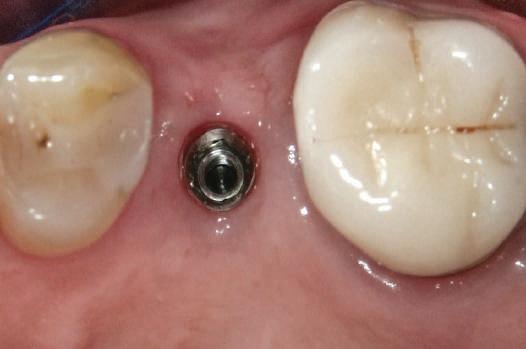

Alt caz (1) Figurile

4. După osteointegrarea implantului 2.4., s-a observat recesia în etapa de amprentare a implantului 2.5.; s-a decis reprepararea marginilor bontului individualizat CAD/CAM 2.4. Înainte de preparare s-a aplicat şnur de retracţie pentru a evita lezarea ţesutului şi a îmbunătăţi vizibilitatea dintelui 2.3. şi a marginii bontului implantar individualizat. Aşa cum era de aşteptat, recesia a fost mai mare de-a lungul versantului distal al bontului 2.4. adiacent locului de extracţie vindecat/cu implantul mai nou.

5. Bontul individualizat aplicat (2.5.) cu bontul repreparat anterior (2.4.). Nu a survenit recesie nouă de o perioadă de peste 3 ani.